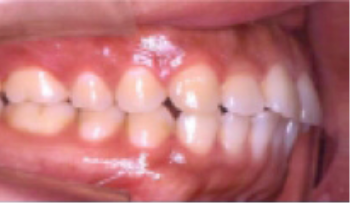

• 상악 전돌(돌출) 위턱이 앞으로 나옴.

Before

After

• 총생(Crowding) 치아가 삐뚤게 남.